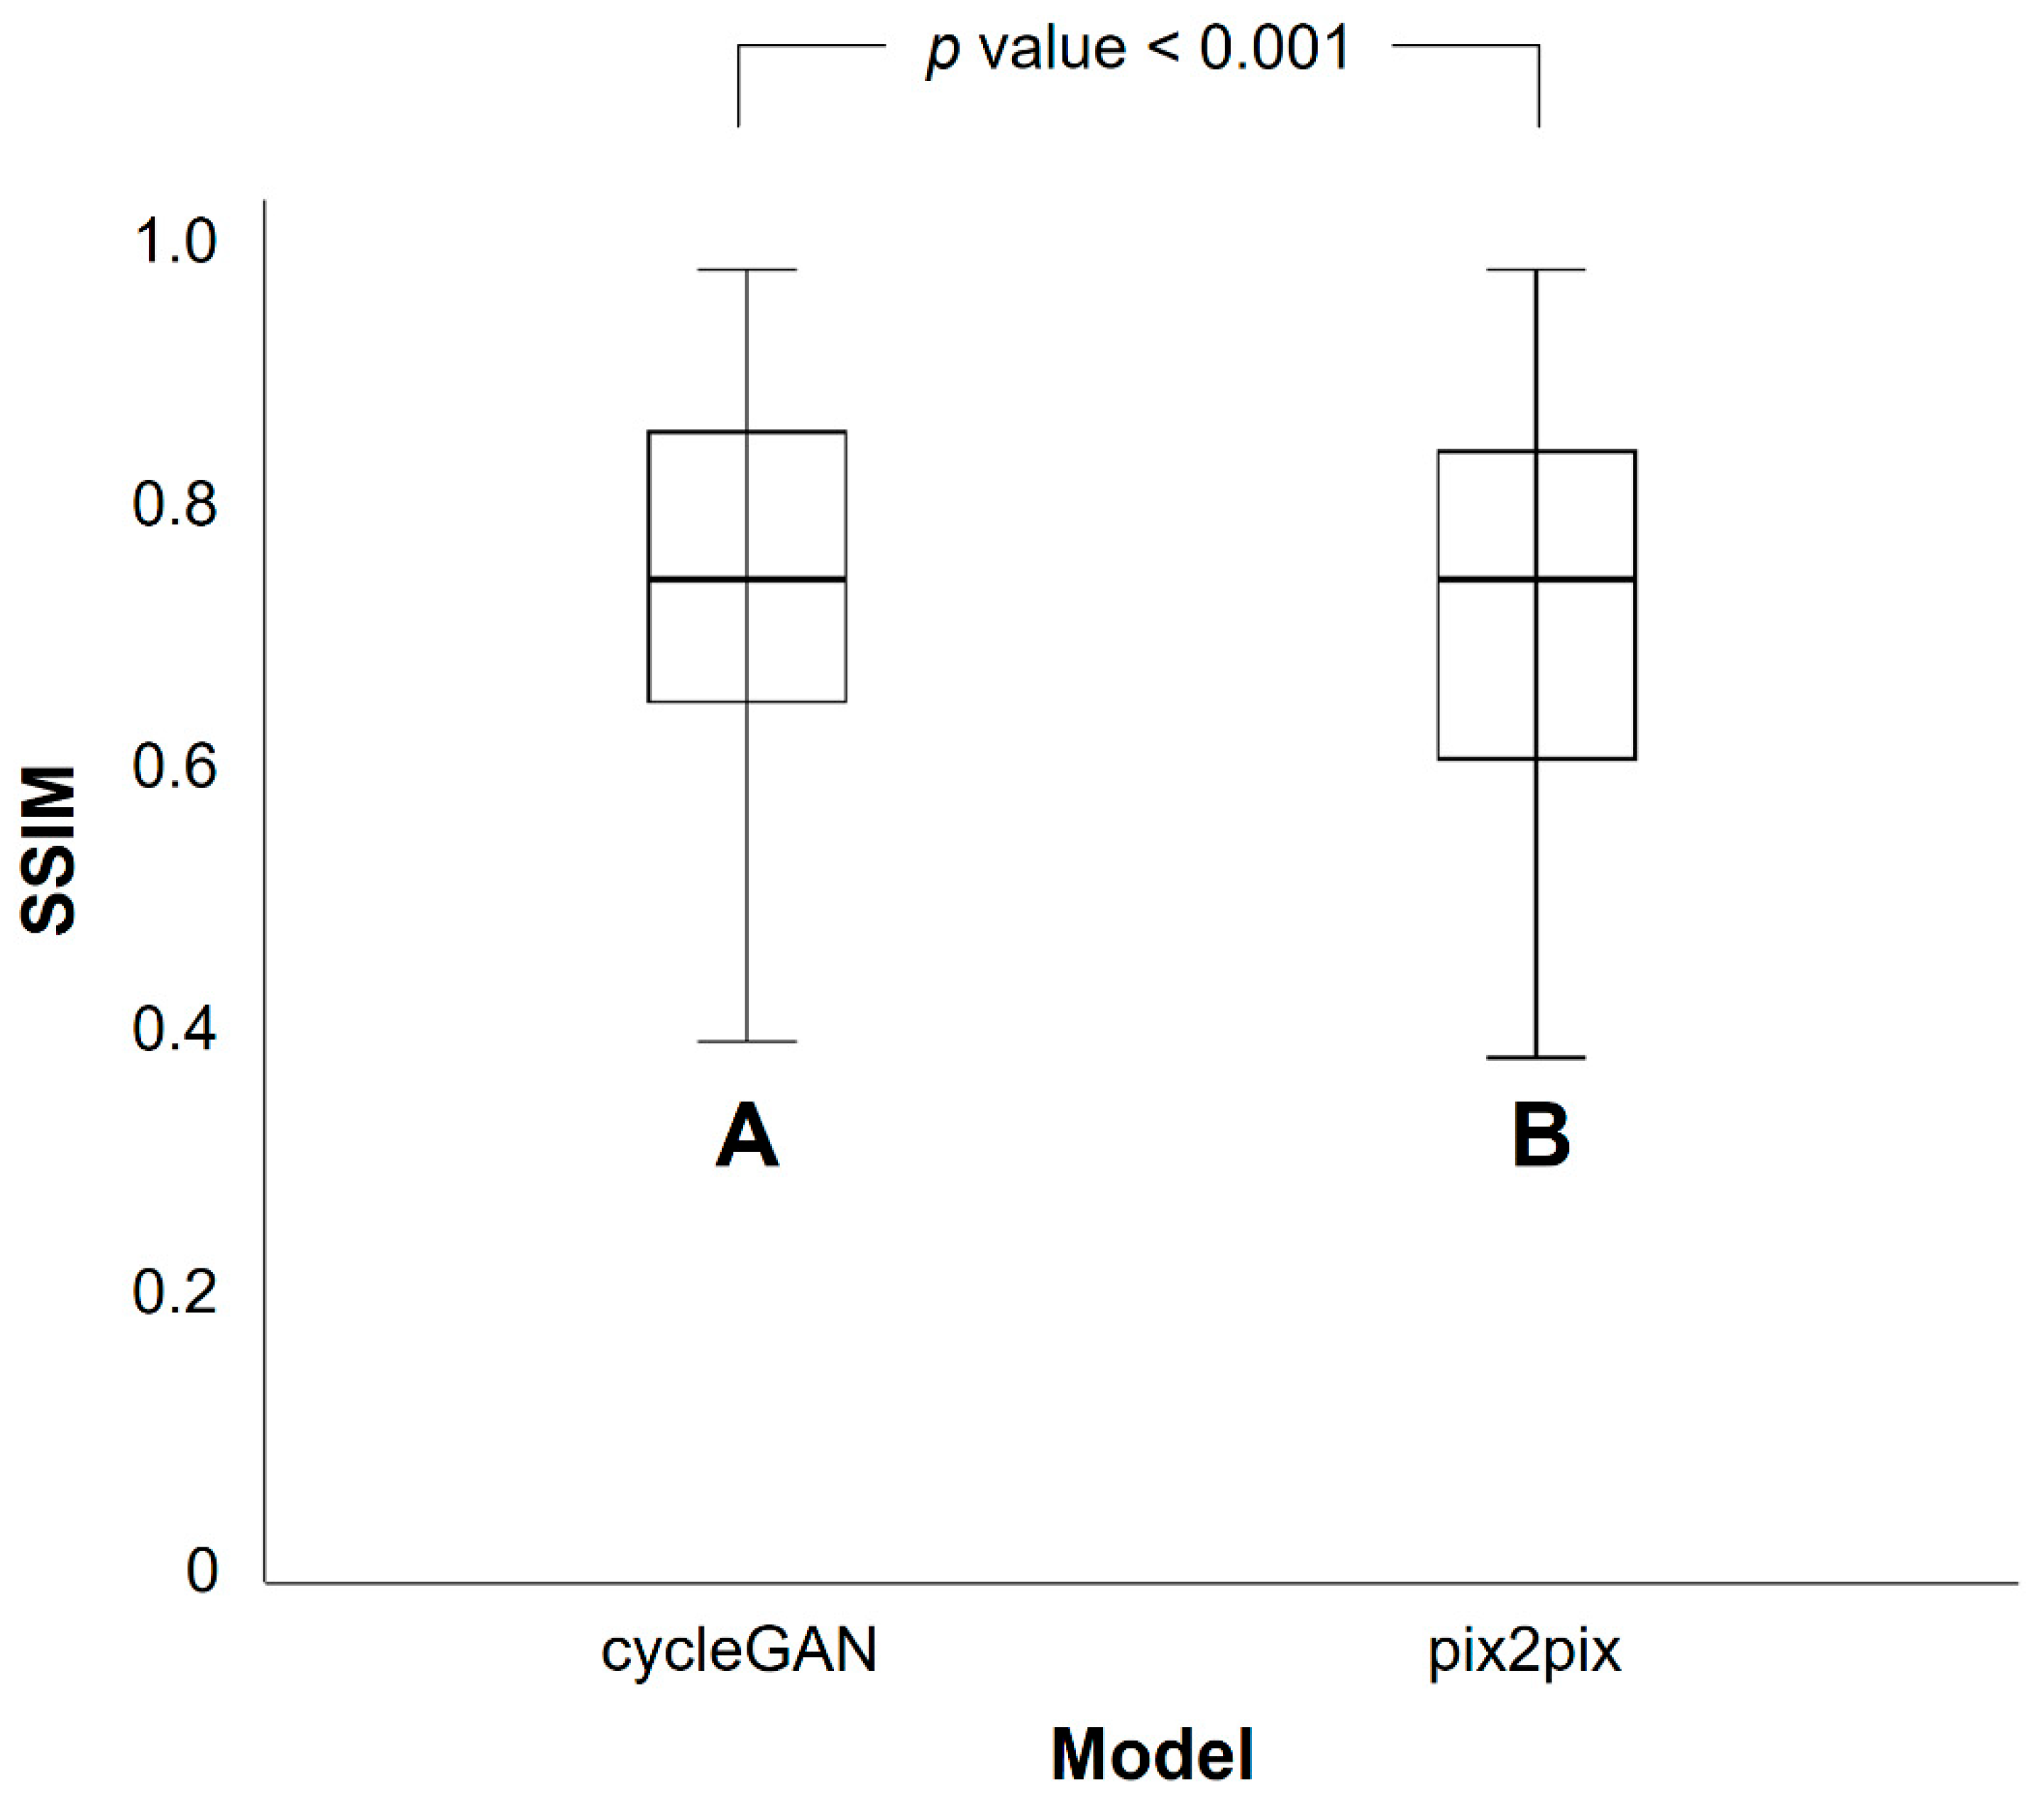

3.2. Differences in SSIM and PSNR Values between PETRE-FDG and PETGE-FDG Images

| CycleGAN Model | Pix2pix Model | p Value * | |

|---|---|---|---|

| Mean | 0.768 | 0.745 | <0.001 |

| Standard deviation | 0.135 | 0.143 |